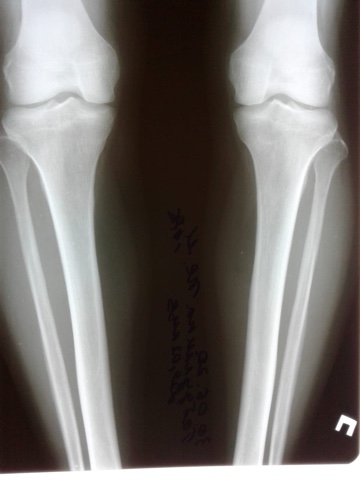

Дата операции -- 03.07.2020

Дата снятия аппаратов 22.10.2020